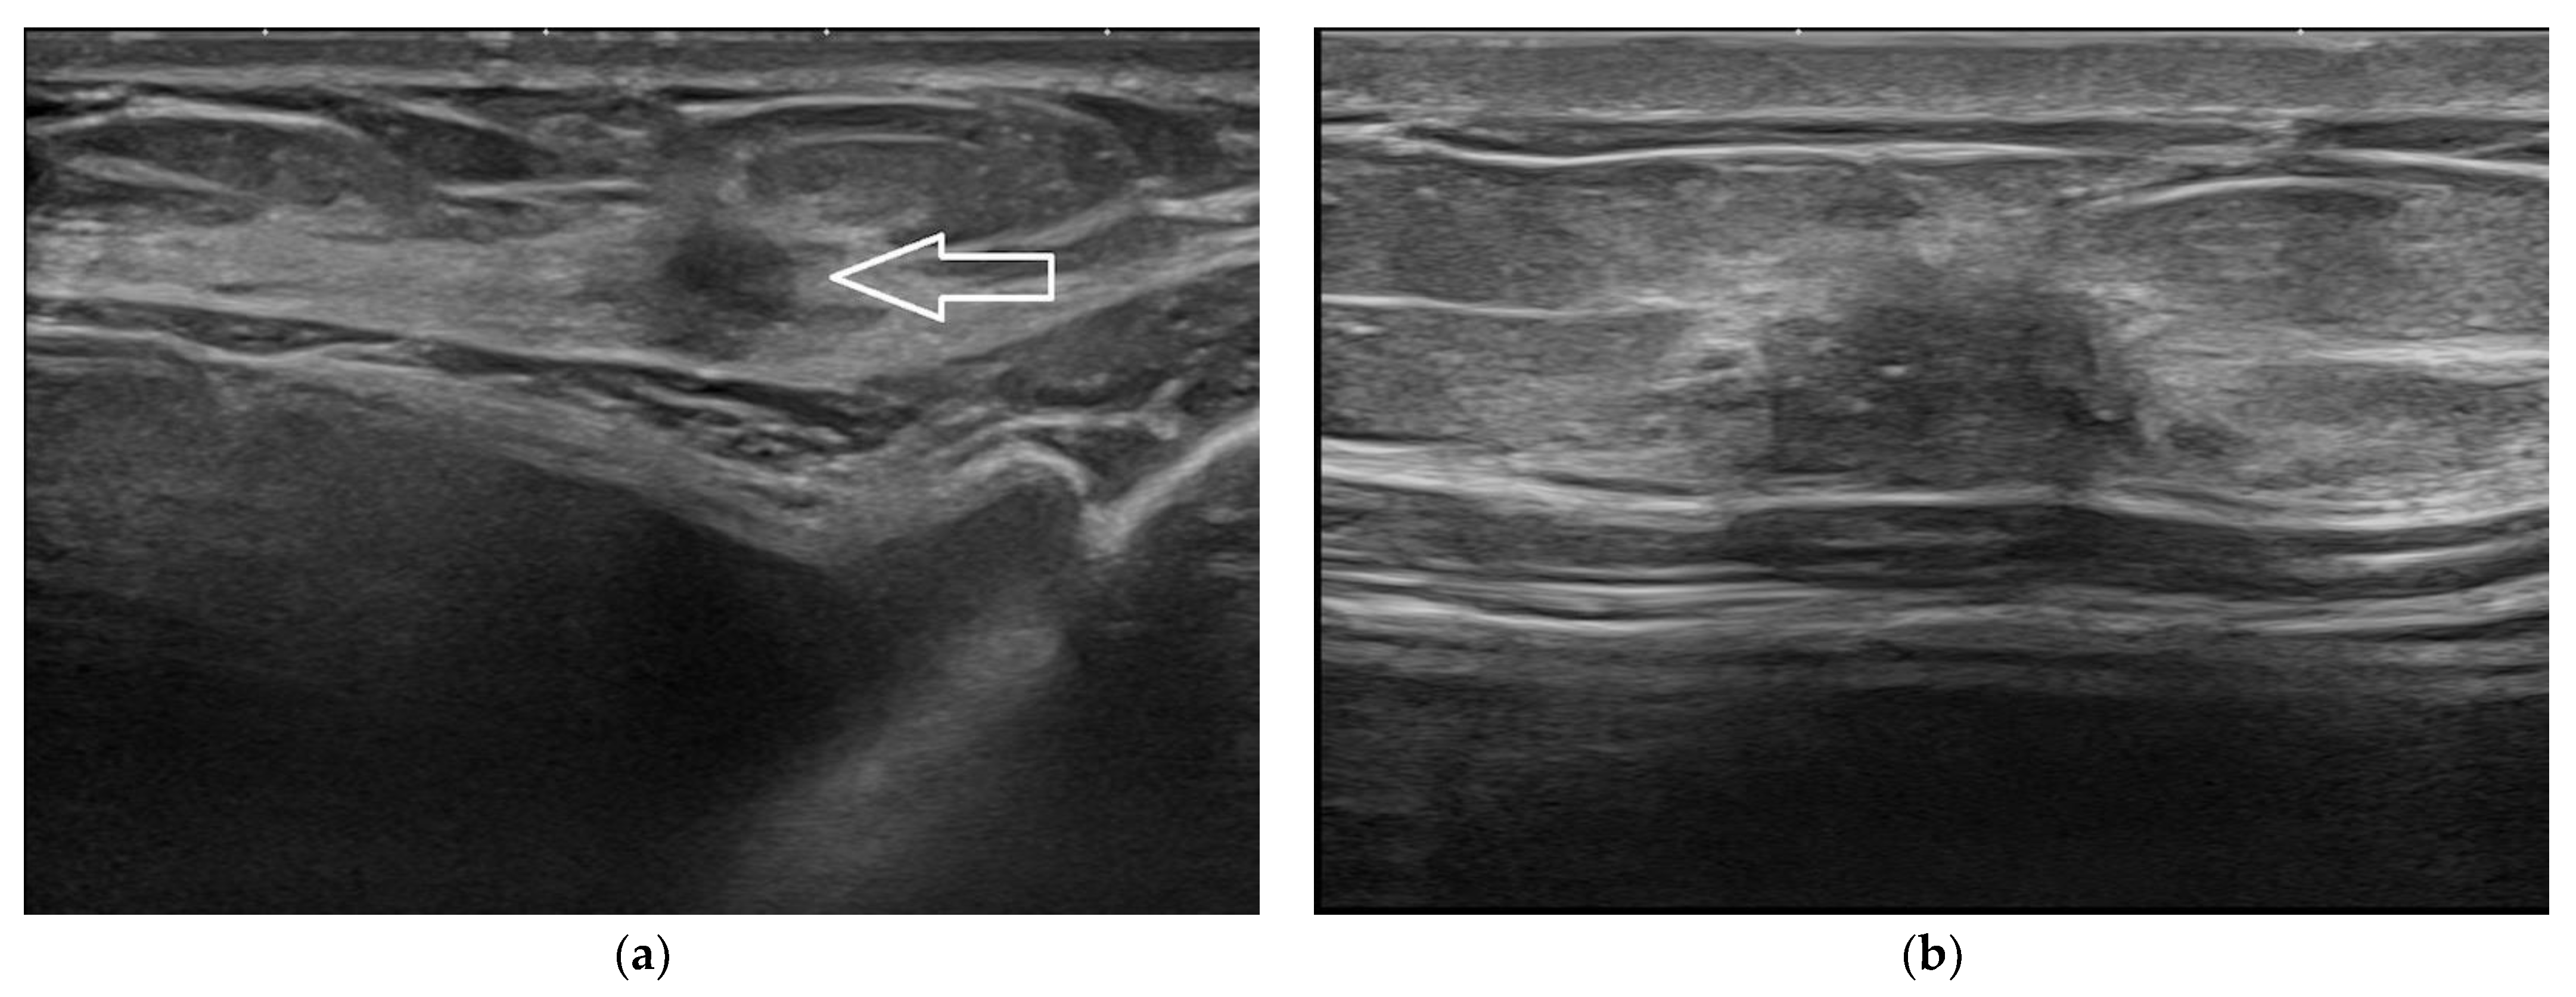

Figure 6. Intraductal papilloma. Retroareolar, oval hypoechoic nodule without flow signals (8 × 4 mm). Appearance at 15 MHz (a). When imaged at 22 MHz (b), the lesion is clearly located in the lumen of a duct and exhibits some internal vessels under power-Doppler imaging.

Ductal ectasia is a frequently encountered abnormality (Figure 5). Intraductal lesions include solidified secretion, ductal hyperplasia, intraductal papilloma, and carcinoma (both in situ and invasive) (Figure 6) [17,18]. The specificity of sonography in differentiating these abnormalities is low (33%), as most lesions are small and have overlapping features [17]. Malignant lesions are usually larger, with non-circumscribed margins, mixed hyperechoic–hypoechoic or complex echogenicity, and significant vascularity [17]. Recognizing intralesional flow signals allows a solidified secretion to be ruled out. On the other hand, the more the vascularization is detected, the more the suspicion of malignancy will be, prompting biopsy. Being very sensitive to slow flows, SMI has proven effective in the characterization of intraductal lesions. SMI with the Vascular Index tool, which allows the quantification of the number of colored pixels within the color box, yielded a sensitivity of 71% and a specificity of 49% in the prediction of malignancy in intraductal lesions [18].